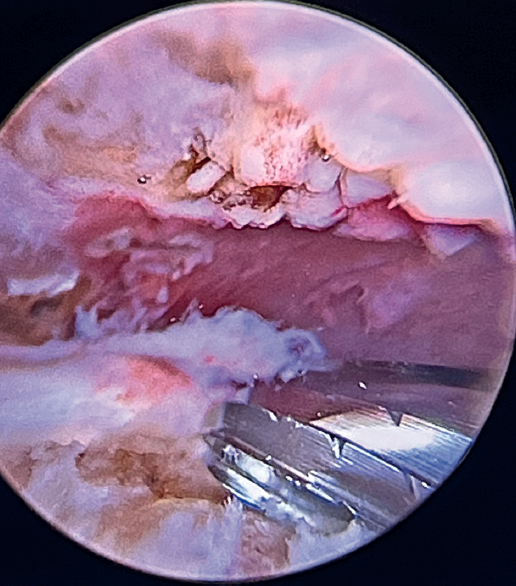

Using penetrating forceps through the anterior portal, the surgeon penetrates the LPB and retrieves one of the suture threads, performing a self-locking Lasso suture in the same step. This is done with two of the three anchoring threads to ensure a correct LPB grip to the footprint of the greater tuberosity and that the tendon does not fray; we do not cut the two threads after knotting (Figures 4, 5 and 6). We also consider it very important to apply the biceps tendon, keeping it as flat and anatomical as possible, avoiding twisting or excessive distension of the tendon. Subsequently, a tenotomy of the LPB distal to these sutures is performed (Figure 7), thus allowing the LPB to function as a superior capsular reconstruction, restricting the ascent of the humeral head.